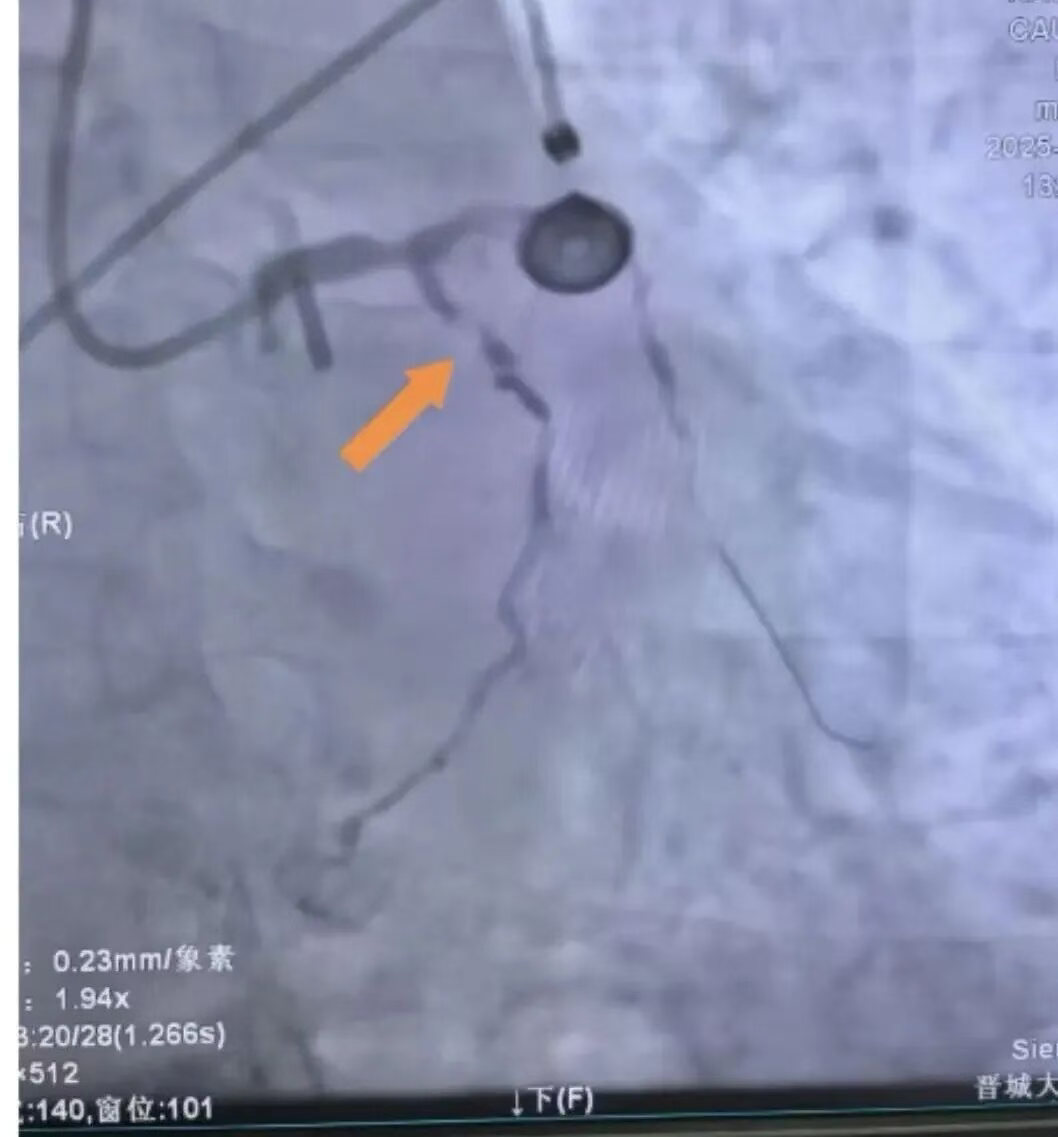

三支主要冠状动脉中,前降支近段完全闭塞,右冠脉亦已闭塞,回旋支近段狭窄达90%,心脏仅靠极微弱的侧支循环维持供血,患者随时可能因心源性休克或恶性心律失常猝死。

手术前